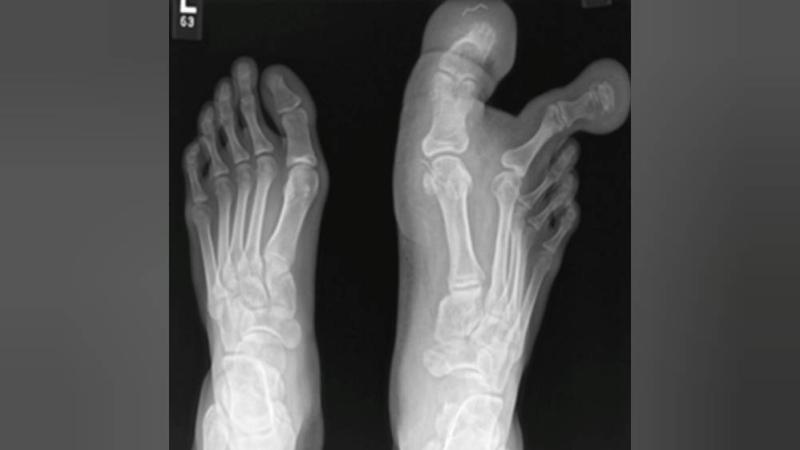

في حالة نادرة، تم تشخيص طفلة بأنها مصابة بالحثل الشحمي الكبير (MDL)، وهو عيب خلقي تسبَّب في عملقة إصبعين في قدميها، فأصبح من الصعب عليها المشي وارتداء الأحذية، قبل أن يتدخل الأطباء جراحياً لعلاجها.

وجاء هذا العيب الخلقي لدى الفتاة البالغة من العمر 12 عاماً، نتيجة توسع العظام والأنسجة والأعصاب في إصبع القدم الكبير والثاني في قدمها اليمنى، وفقاً لصحيفة «ذا صن» البريطانية.

من جانبه، قال جراح العظام في المركز الطبي في جامعة كيبانجسان الدكتور سري أرون سيلفام: إن «صور الأشعة البسيطة ونتائج التصوير بالرنين المغناطيسي للفتاة كشفت عن تراكم الأنسجة الدهنية حول إصبع القدم الأول والثاني، والجوانب الوسطى والجانبية لمشط القدم الأول، وتمتد حتى القوس الأخمصي الأوسط للقدم».